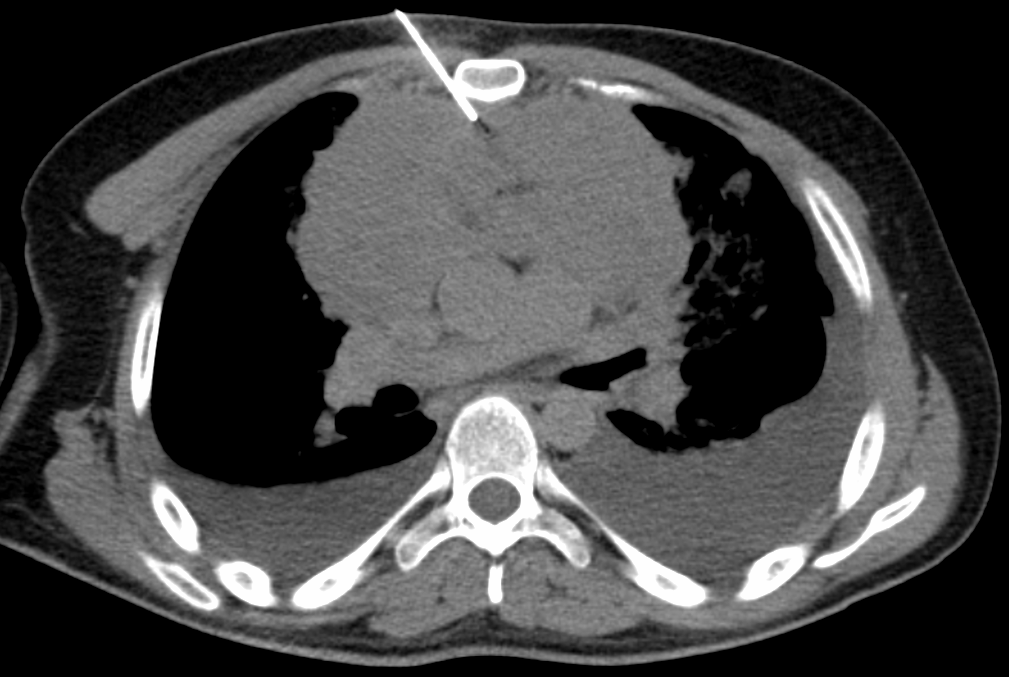

Biopsia de mediastino anterior 2